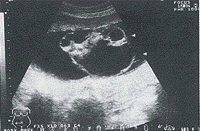

中国超声医学杂志990333 患者,女,25岁,因停经24周来我院常规查孕情。常规查体未发现异常。妇查:子宫底28cm腹围82cm头位,胎心150次/分,规律。B超检查:子宫内胎儿头环规则,双顶径6.0cm。胎心率146次/分,规律,胎位ROA,脊柱颈,胸段呈串珠状排列均匀,在腰、骶椎部呈梭形增宽,横断面呈“八”字形。胎儿四肢未见异常回声。前壁胎盘Ⅰ级,宫内羊水较多最大径11.5cm。胎儿骶尾部突出一略圆球样多囊性包块约9.9cm×8.3cm×8.0cm,边界清,内部示大小不等无回声区。为多囊性改变(图1)。B超诊断:1.胎儿骶尾部囊性包块,畸胎瘤可能;2.脊柱腰骶段披裂。引产胎儿娩出后证实为骶尾部畸胎瘤伴脊柱裂。引产后诊断与术前诊断一致。

图1 胎儿尾骶部畸胎瘤(箭头所示)